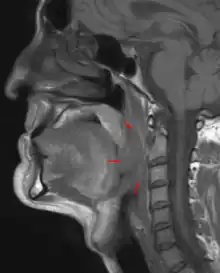

Oropharyngeal cancer,[1][2][3] also known as oropharyngeal squamous cell carcinoma and tonsil cancer,[1] is a disease in which abnormal cells with the potential to both grow locally and spread to other parts of the body are found in the oral cavity, in the tissue of the part of the throat (oropharynx) that includes the base of the tongue, the tonsils, the soft palate, and the walls of the pharynx.[1][2][3][5]